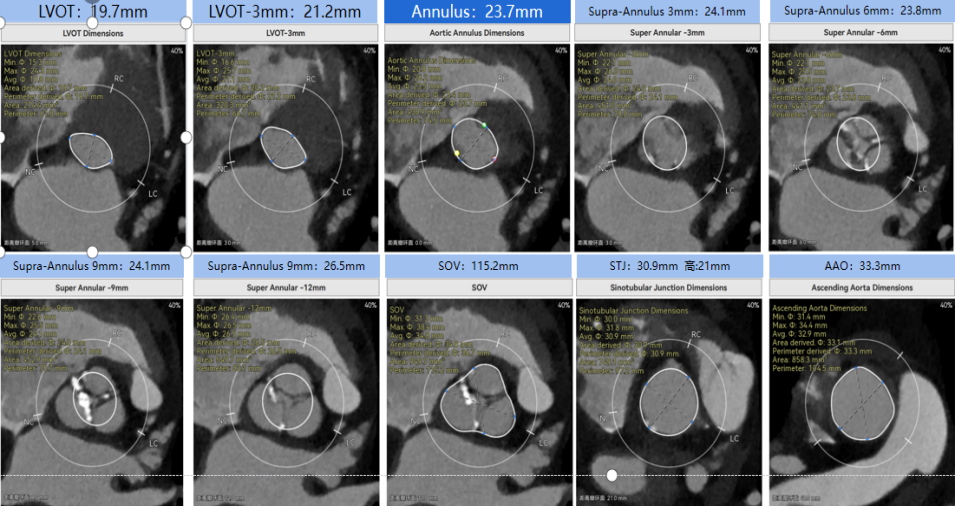

病例概览

患者病史 体检发现心脏瓣膜病半月余,平素无症状 ,有高血压病史。 后来院复查诊断为:主动脉瓣狭窄(重度)、先天性主动脉瓣二叶瓣畸形、心室肥厚、升主动脉扩张心功能 I 级(NYHA 分级)、高血压病 2 级(极高危)。 术前 CT:Type0型二叶瓣,瓣叶增厚,无钙化,类风湿性;瓣环径25.6mm,LVOT稍收窄,瓣环水平夹角66.6°,轻微横位心;左右冠开口高度可,瓣叶不长,无冠脉风险;心室收缩末内径约32mm,室壁增厚;外周入路无明显迂曲,无钙化、双侧内径可、双股中分叉,右侧为主入路能够支持20F大鞘通过。 造影角度及入路:LAO 6° CAU 13° 手术策略 采用右侧股动脉为主入路,左侧为辅助入路,常规穿刺。推荐使用20球囊预扩,预装TAV29瓣膜,初始定位对齐瓣环上0mm开始释放。 手术过程 20号球囊预扩无明显腰征 输送器过弓跨瓣顺滑 80%工作位观察 术后造影,瓣膜释放位置良好,无瓣周漏 术后超声:人工生物瓣释放后形态满意,瓣叶开放、关闭活动良好,无瓣周漏;跨瓣血流速度降至 2.5m/s,平均压力梯度6mmHg,符合手术预期。 Prostyle A®预装干瓣——“刚柔并济”助力临床最优化解决方案: 丝滑过弓能力:Prostyle A®短瓣架设计联合远端超滑亲水涂层,即使没有联合使用snare,都可以柔顺过弓,该例横位心的患者更好的展现了输送系统的柔顺性; 平衡的径向支撑力:该例患者Type0型二叶瓣,术后形态展开良好且无瓣周漏,在横位心等复杂情况下实现稳定锚定。 80%可回收设计:80%工作位观察,起搏时间更短,对患者损伤减少到最小,也利于术中精准调整瓣膜位置,保证术后效果。